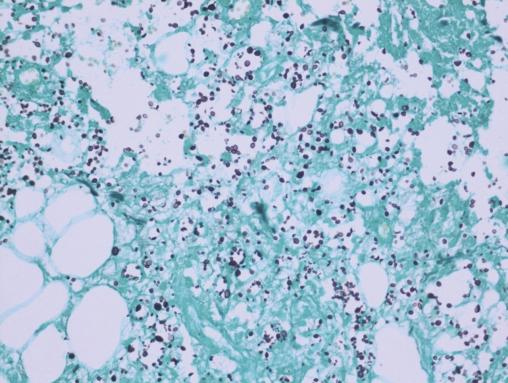

Après quelques jours de traitement immunosuppresseur, une douleur intense et insomniante s’installe, avec érythème et tuméfaction du membre supérieur gauche. Les examens complémentaires retrouvent une protéine C-réactive (CRP) à 300 mg/L, des hémocultures stériles, une échographie Doppler artérioveineuse sans thrombose. Le diagnostic d’une dermohypodermite bactérienne non nécrosante est évoqué dans un premier temps. La patiente est alors traitée par antibiothérapie (amoxicilline et acide clavulanique). L’évolution est défavorable, avec apparition de lésions nécrotico-hémorragiques rapidement extensives (fig. 2 ). Une imagerie par résonance magnétique (IRM) [fig. 3 ] montre une infiltration des parties molles sous-cutanées, des loges musculaires associées à des bulles d’air, en faveur d’une fasciite nécrosante. Une exploration chirurgicale permet de réaliser des biopsies profondes au niveau du fascia et du muscle. Le résultat histologique, après coloration de Grocott, montre une cryptococcose avec multiples foyers de nécrose de liquéfaction (fig. 4 ). Le diagnostic de fasciite nécrosante cryptococcique est finalement retenu. La recherche de l’antigène sérique cryptococique est positive (1 : 2 000, test d’agglutination au latex). La sérologie VIH (virus de l’immunodéficience humaine) est négative. À défaut d’amphotéricine B, du fluconazole à la dose de 400 mg/j est administré. L’évolution a été défavorable, avec décès à la suite d’un choc septique.